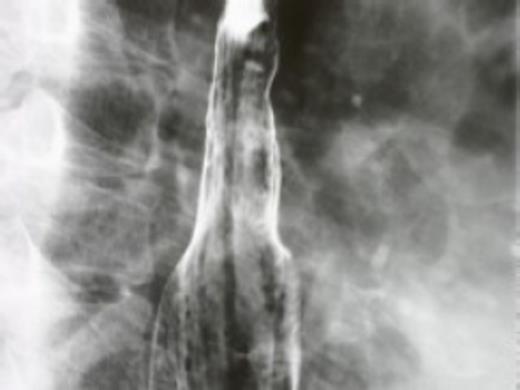

Under general anesthesia in the left lateral position, a thoracoscopic approach was utilised to evaluate and remove the lesion. A cyst was found within the oesophagus wall. The oesophagus wall was carefully dissected, and the cyst was successfully excised. There were no fistulas between the oesophagus and the cyst. Care was taken to avoid breaching the mucosa of the oesophagus, and intraoperative oesophagogastroscopy with a flexible fiberoptic scope confirmed there was no oesophageal injury. Initially, the defect of the oesophageal wall was repaired with sutures, which resulted in mild stenosis of the oesophagus. Some sutures were removed, and a pedicled intercostal muscle flap was prepared to cover the defect completely. All procedures were carried out by VATS with three ports, with a small incision extended to facilitate harvesting the intercostal muscle flap. The cyst measured 30–20–12 mm and had ciliated epithelium, confirming the diagnosis of a bronchogenic cyst. The patient's postoperative course was uneventful, but he felt that ingested food remained in the oesophagus. These symptoms subsided gradually without treatment. Barium swallow tests in the perioperative period showed dilatation of the lower oesophagus, which recovered to almost normal within 4 years (Fig. 2).